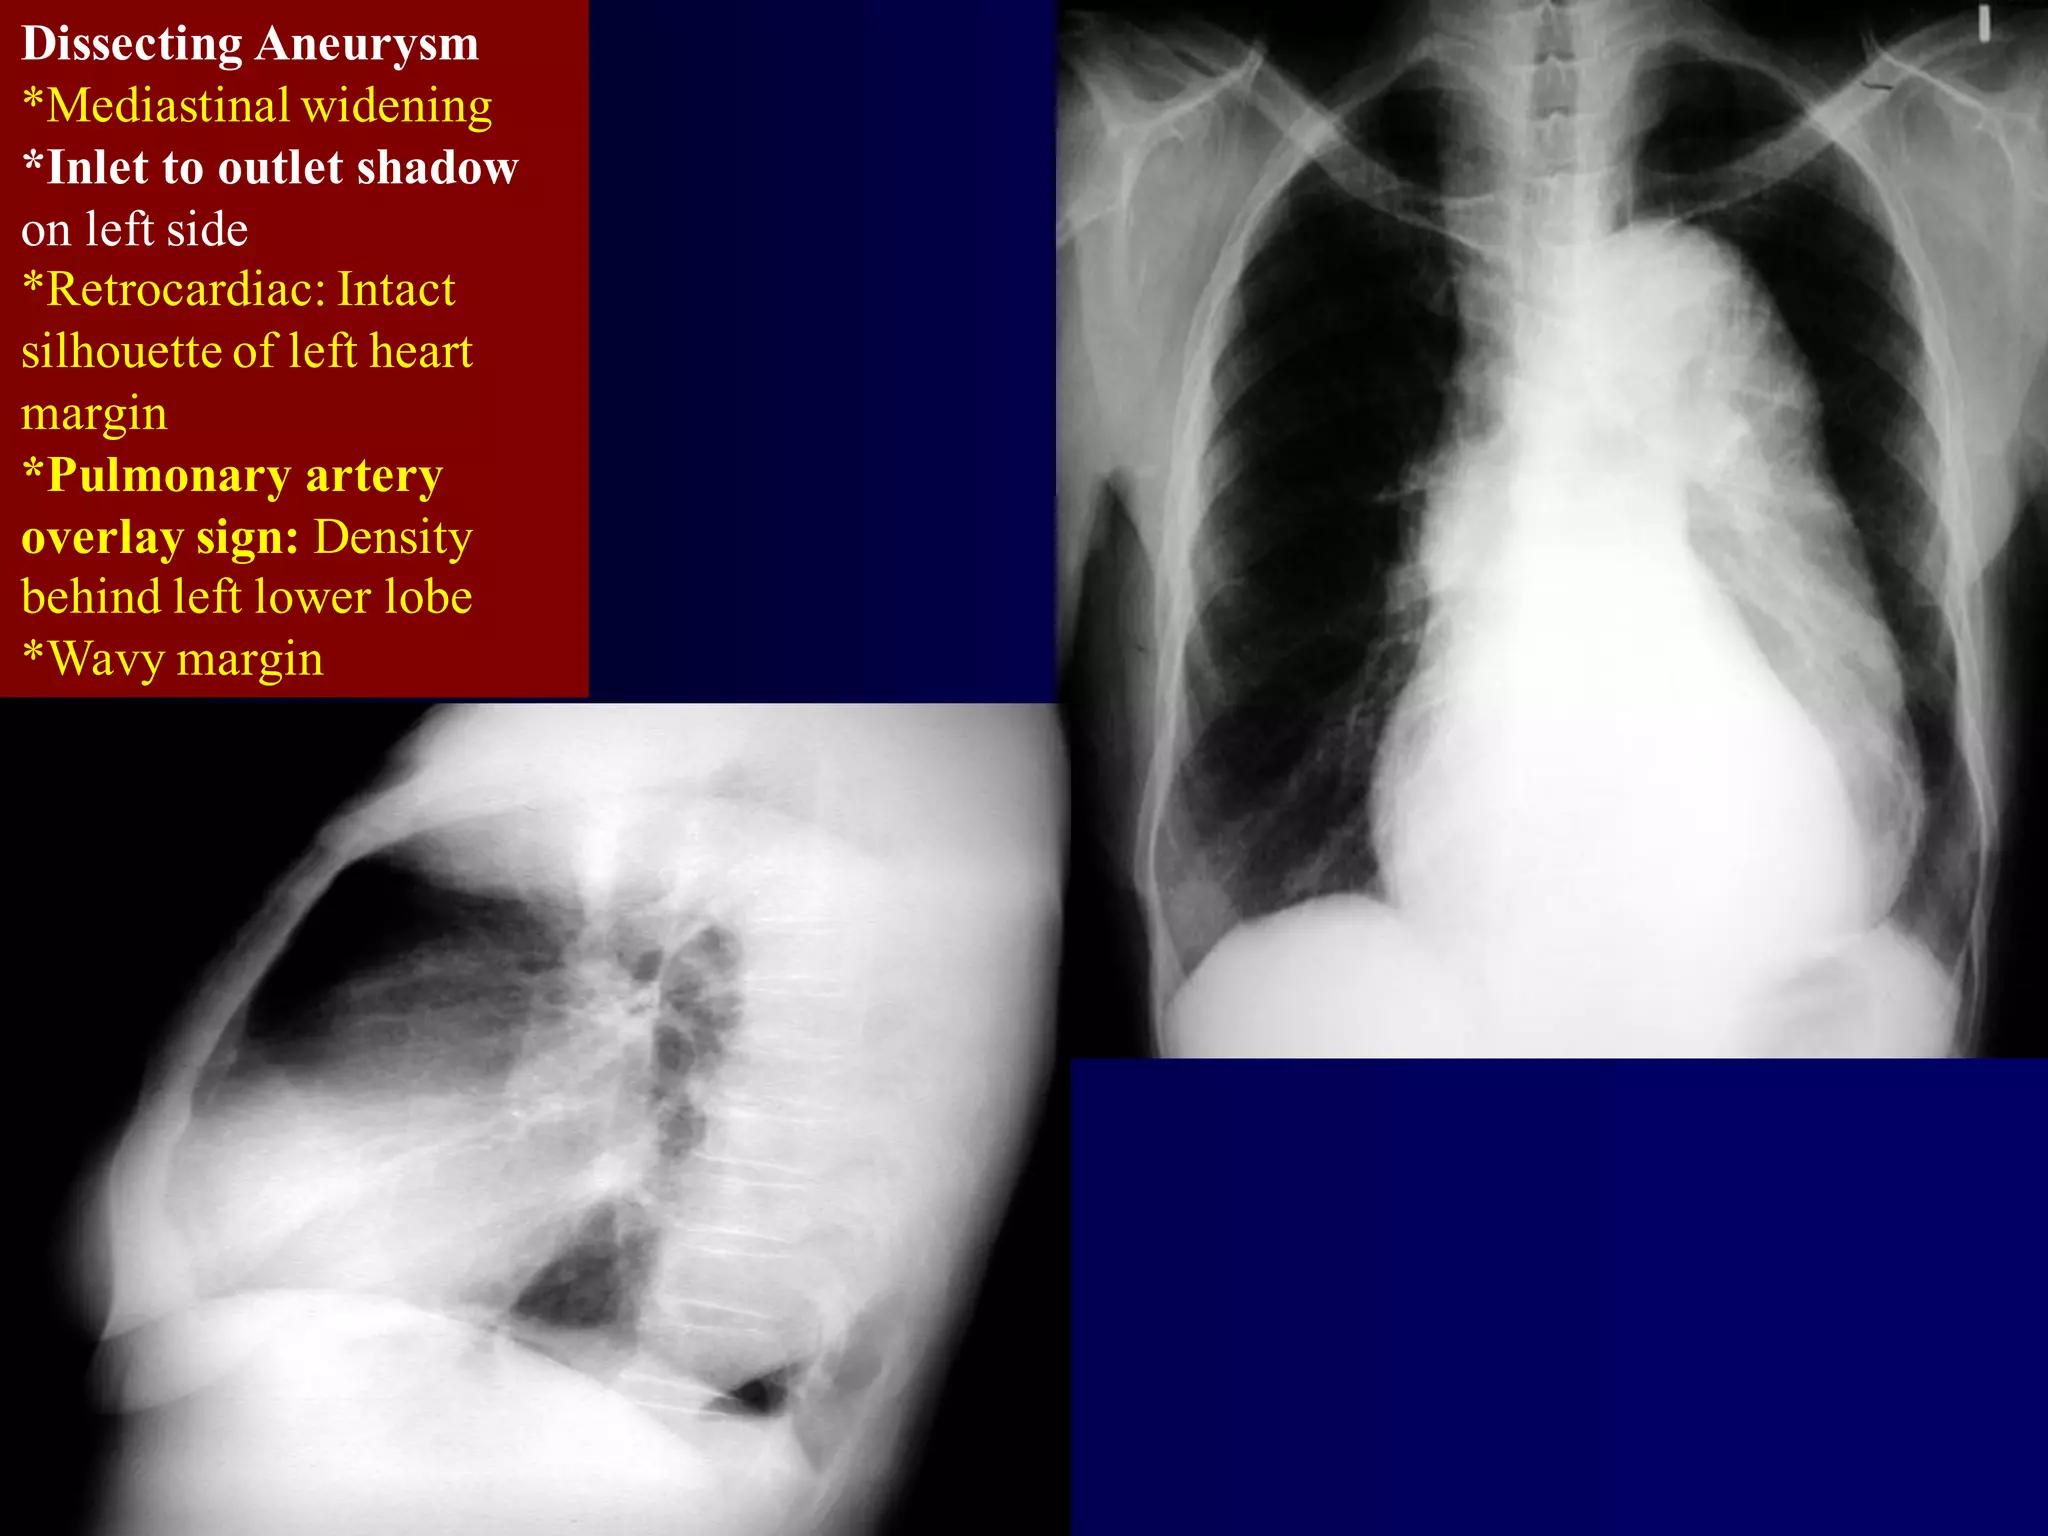

Dissecting Aneurysm

*Mediastinal widening

*Inlet to outlet shadow

on left side

*Retrocardiac: Intact

silhouette of left heart

margin

*Pulmonary artery

overlay sign: Density

behind left lower lobe

*Wavy margin